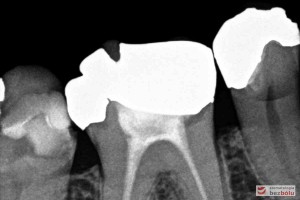

Do naszej placówki zgłosiła się starannie planująca swoje działania Europejka, mieszkająca na stałe w Kotlinie Jeleniogórskiej. Jej oczekiwania dotyczyły bardzo metodycznie zaplanowanego planu leczenia. Celem jaki postawiła przed naszym zespołem lekarzy było wyeliminowanie wszystkich wątpliwych i nierokujących wypełnień, a także poprawa estetyki w zakresie lewego siekacza centralnego w szczęce. Został rozpisany blisko dwuletni plan wymiany zużytych i nieszczelnych wypełnień amalgamatowych i kompozytowych. Zaplanowano również przygotowanie endodontyczne wybranych zębów w szczęce i żuchwie, a także zaopatrzenie w inlay’e porcelanowe i korony ceramiczne wykonane w systemie e-max.